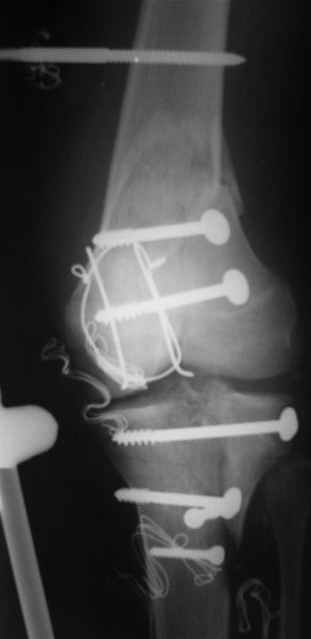

№4 снимок через два дня после операции, супракондилярный перелом, при поступлении конечность была холодная и без пульса, подозрение на повреждение сосудов, сделана ABI (ankle-brachial index) в приемном отделении, индекс меньше 1 к 0.9 в норме 1 к 1.1, срочная ангиография в операционной после Ex-Fix, по два стержня в сегменте наложен в течение 20 мин, повреждение подколенной артерии, ушивание сосудистым хирургом через медиальный доступ в дистальном отделе бедра и двухразрезная профилактическая фацсиотомия, перкутанная фиксация каннюлированными шурупами несмещенного перелома шейки бедра и дополнительные стержни в фиксаторе для жесткости.